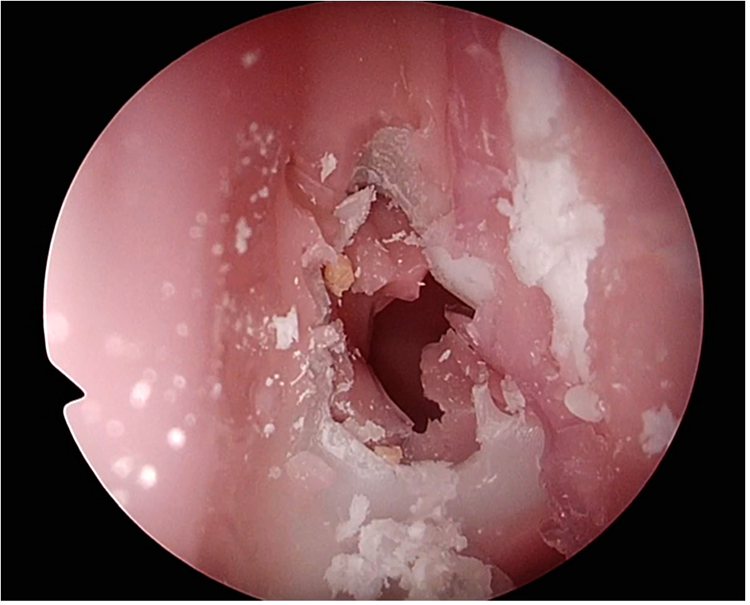

Step (1) on the TNS Box is demonstrated in

Figure 3and anterior sphenoidotomy in

Figure 4.

Figure 4

Anterior sphenoidotomy performed on the TNS Box.